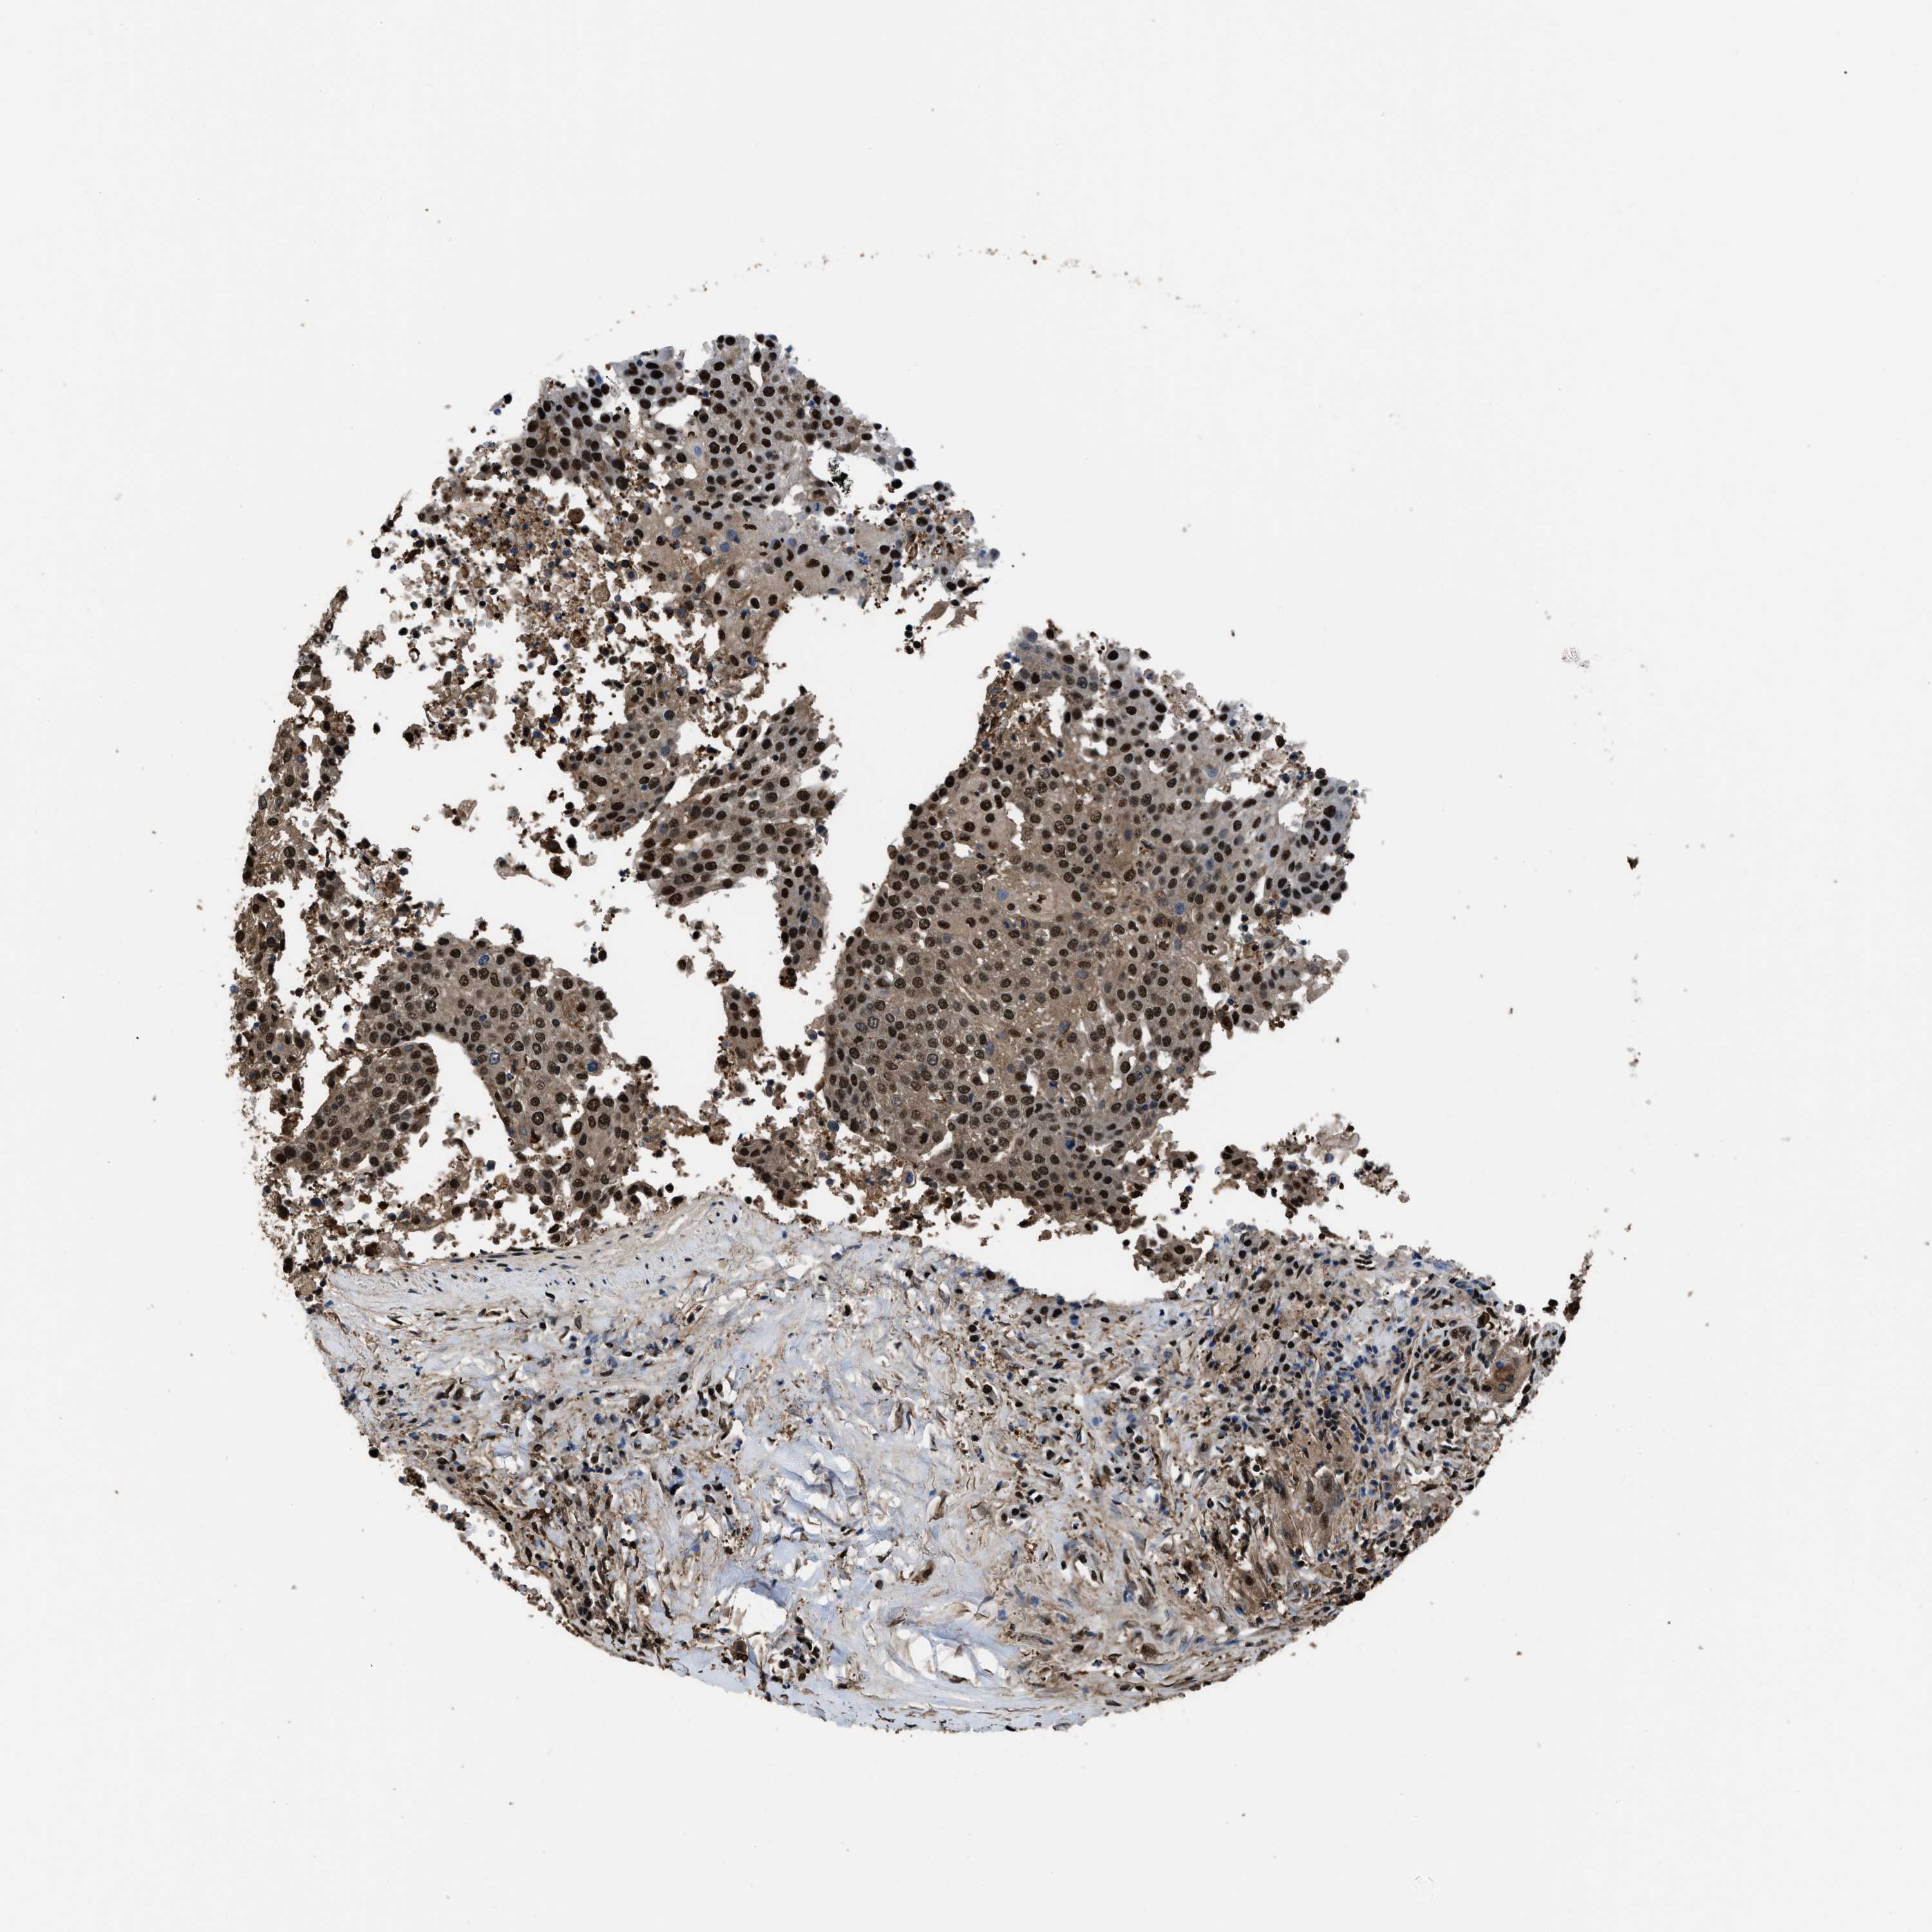

UROTHELIAL CANCER - Protein expressioni

A mouse-over function shows sample information and annotation data. Click on an image to view it in a full screen mode. Samples can be filtered based on level of antibody staining by selecting one or several of the following categories: high, medium, low and not detected. The assay and annotation is described here.

Antibody stainingi

Antibody staining in the annotated cell types in the current human tissue is reported as not detected, low, medium, or high, based on conventional immunohistochemistry profiling in selected tissues. This score is based on the combination of the staining intensity and fraction of stained cells.

Each image is clickable and will lead to virtual microscopy that enables deeper exploration of all samples and also displays staining intensity scores, fraction scores and subcellular localization as well as patient and tissue information for each sample.

Antibody HPA018830

Antibody CAB010149

Staining

High

Medium

Low

Not detected

Intensity

Strong

Moderate

Weak

Negative

Quantity

>75%

75%-25%

<25%

None

Location

Nuclear

Cytoplasmic/membranous

Cytoplasmic/membranous,nuclear

Urothelial carcinoma, Low grade

Urothelial carcinoma, High grade